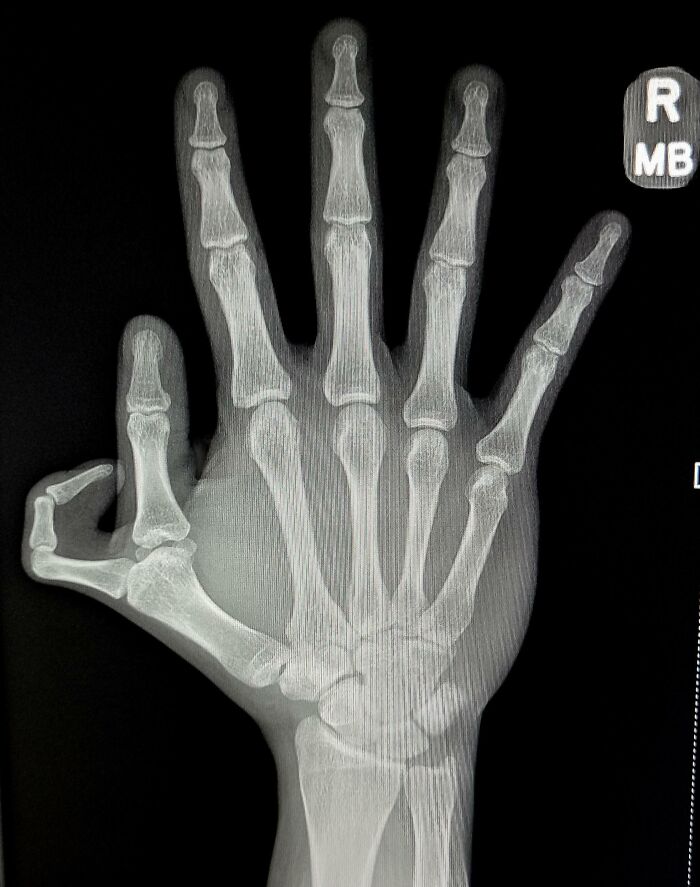

万国アノニマスさん

俺は生まれつき4本指だ

万国アノニマスさん カートゥーンの世界から来たのかな?

万国アノニマスさん シンプソンズの世界の住人だな!